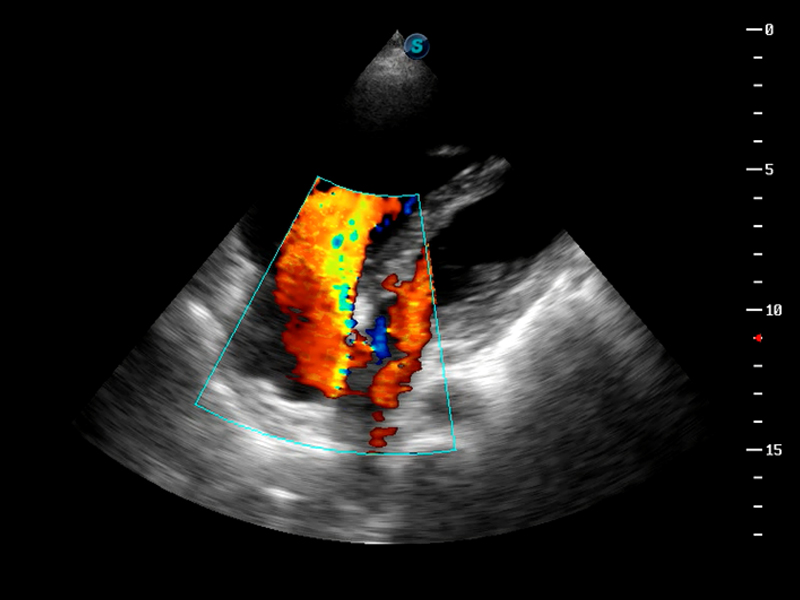

S9便携式彩色多普勒超声诊断仪是球速体育入口研发的高端便携彩超设备,外观设计新颖、产品性能卓越。S9在便携超声领域采用了突破传统的触摸屏交互设计,并以先进的软件硬件技术和设计理念,为您带来清晰的图像质量、稳定的工作性能和便捷的操作体验。

成像技术

AutoC智能血流追踪